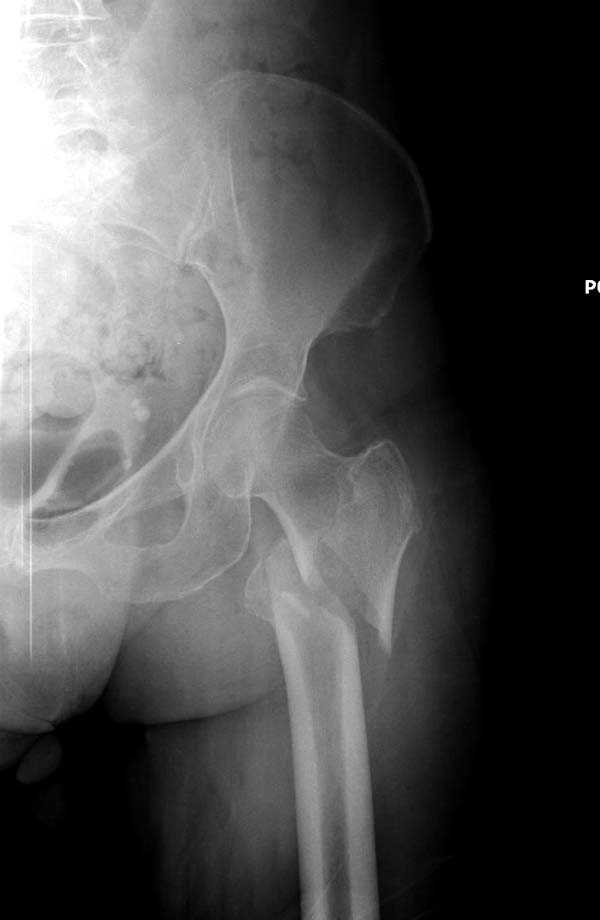

Здесь представлен случай, где в послеоперационном периоде обнаружена техническая ошибка, Gamma 3 установлен с нарушением методики. Больная в 91 лет, прооперирована через день после поступления и выписана через 48 часов.

При первом послеоперационном поликлиническом осмотре больная предъявила жалобы на боли в бедре. В серийных снимках обнаружен продольный перелом верхнего отдела бедра.

Считаем, что техническая ошибка произошла во время установки гвоздя, когда рассверливанию канала не уделили должного внимания. Канал остался узковат, и гвоздь был забит с силой. Полная нагрузка конечности приостановлена на две недели, и боли в конечности изчезли. Больная начала нагрузку и перелом срастается.-- Djoldas Kuldjanov, M.D.Associate ProfessorDepartment of Orthopedic SurgerySt. Louis University

I have a different interpretation of this case. I suspect you did not tighten the set screw all the way in order to allow sliding of the lag screw and fracture fragment compression, as you would for a standard intertrochanteric hip fracture. This is a reverse obliquity fracture, so the result is migration of the proximal segment. I doubt reaming the canal would have prevented this. Had the set screw been fully tightened, there would be no postoperative fragment motion.

I looked at the films again and saw that you are referring to the nondisplaced shaft fracture, not the proximal fragment position. Sorry.

Мне тоже представляется, что это не единственная проблема. Продольные трещины заживают легко и быстро. Интересно, почему увеличился варус и

появилась медиализация дистального отломка.

Мне думается, что варусное положение проксимального отломка на последующих снимках не более чем проекционный феномен. Раскол же диафиза вдоль, наверняка, связан с чрезмерно насильственным введением штифта. Вообще, при реверсивных, да и обычных вертельных переломах, многие давно отказались от короткой Гаммы в пользу long-версии. Но в любом случае надо быть на 100 уверенным в подготовке канала.

Перелом А3, подвертельный, вероятно, на длинной версии гвоздя такого бы не произошло

eto nestabil'nui perelom. nado bylo stavit' gamma long. kanal uzkii (bylo vidno). mesiaz ne nagrujat', vse srastetsia!